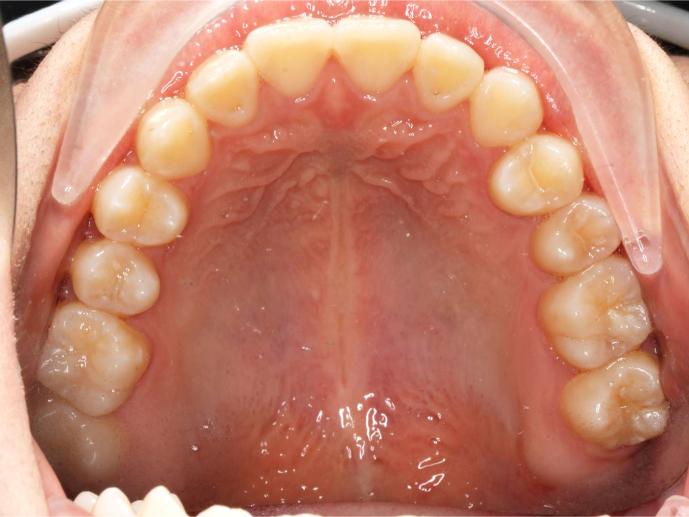

Before and After Images